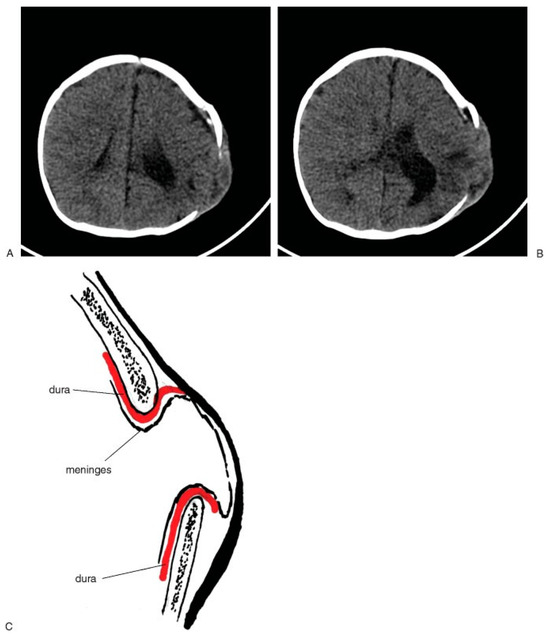

When the delivery is a particularly traumatic one, cranial fractures can occur. As a potential consequence, an unusual phenomenon called ‘‘pseudo-growth’’ of the skull fracture may occur in some children. This skull fracture radiologically and clinically seems to enlarge slowly over a period of 1 to 6 months after the fracture has occurred. A palpable bone defect with protrusion of the meninges develops as the dura separates. In some patients, the defect is large enough to require bone grafting. In other patients, the pseudo-growth of the skull can be seen on radiological studies (Figure 2A,B). In other cases, the defect is small or very limited and may not always be identifiable clinically but can be noted by palpation. Radiographic appearances, however, are not always a guide to treatment. It is the clinical examination of the integrity of the skull that dictates the need for calvarial reconstruction. Some deformity is due to a dural laceration with expansion of the remainder of the meninges and brain through the dural defect with pressure causing bone resorption. Surgical repair requires at least dural repair and possibly bone reconstruction depending upon the age of the patient. [1,2] Once the patient is over a year old, the efficiency of periosteal reformation of the bone is less predictable. In these cases, bone grafting is required. The use of absorbable plates and screws allows less negative influence on the healing of the reconstructed site and less potential deformity. [3,4] Some authors recommend routine radiological follow-up 1 year after any skull fracture to document the appearance of the pseudogrowth defect. [1,2]

Figure 2. Fractures resulting in pseudogrowth are often seen long after the injury and result in the need for surgical correction with repair of the fracture, repair of the dural tears, and grafting of the bone (A,B). The defect is prevented from healing by the dural tears with herniation of the meninges (C).